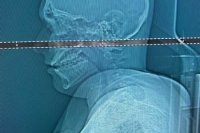

Študent mal 4 dni v lebke zaseknutý projektil z pištole